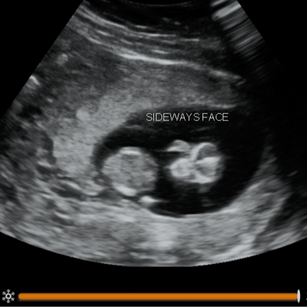

11 Weeks Pregnant

Size: ~1.5 inches (4 cm), the size of a Fig!

Eyes, nose, mouth, and ears more distinct.

Baby can make small movements of head and limbs.